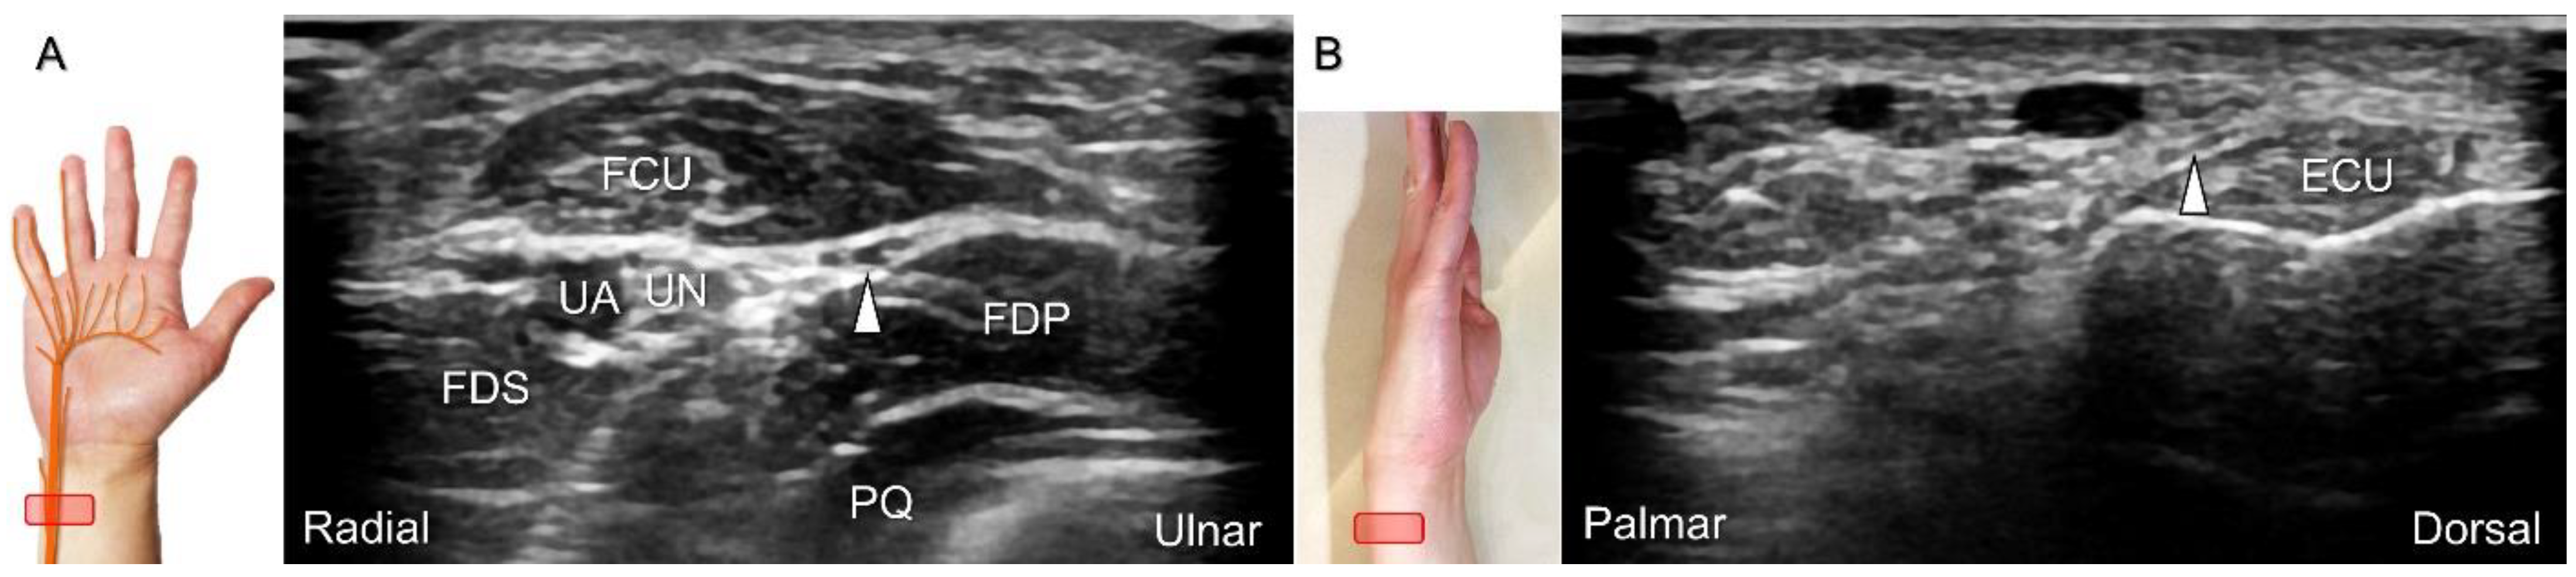

Figure 19. Sonographic imaging of the dorsal ulnar cutaneous nerve as it branches from the ulnar aspect of the ulnar nerve underneath the flexor carpi ulnaris (FCU) muscle (A). The nerve wraps around the distal ulna to reach the dorsal wrist (B). Arrowhead: dorsal ulnar cutaneous nerve. UN: ulnar nerve; UA: ulnar artery; FDS: flexor digitorum superficialis muscle; FDP: flexor digitorum profundus muscle; PQ; pronator quadratus muscle; ECU: extensor carpi ulnaris tendon.

Scanning Technique

With the forearm in supination, the transducer is placed on the distal third of the ventral forearm to locate the myotendinous junction of the FCU. The dorsal ulnar cutaneous nerve branches from the ulnar aspect of the ulnar nerve underneath the FCU, and then wraps around the distal ulna to reach the dorsal wrist. Moving the transducer to the dorsal wrist, the nerve can be seen coursing above the extensor carpi ulnaris tendon (Figure 19), toward the dorsal ulnar wrist and hand region.

Clinical Implication

The causes of damage/entrapment of the dorsal ulnar cutaneous nerve include compression over the distal forearm by a bracelet or a metal implant, extensor carpi ulnaris tenosynovitis, or triangular fibrocartilage complex injury [43]. For hydrodissection of the entrapped nerve (Figure 20A–C), the in-plane approach targeting its short axis is preferred (Figure 20D).